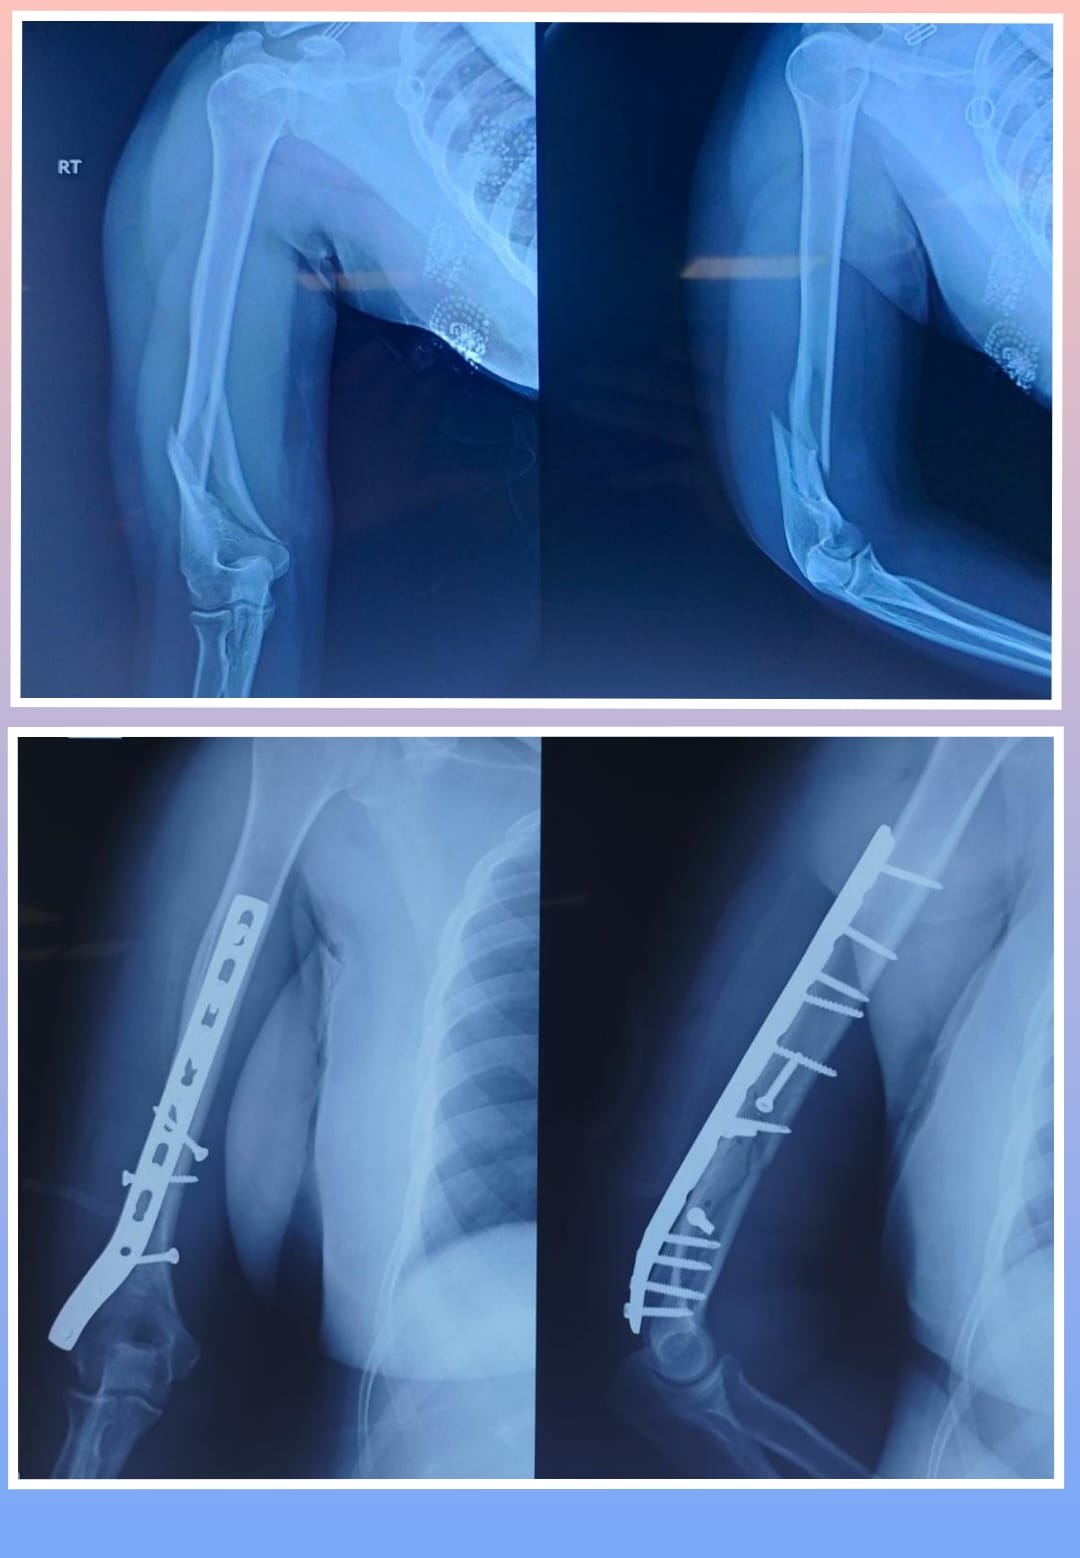

X-ray

Warning: Graphic Content

The following section contains graphic images of surgical procedures. These images are intended for educational purposes and may be disturbing to some viewers. Viewer discretion is advised.

Surgeries